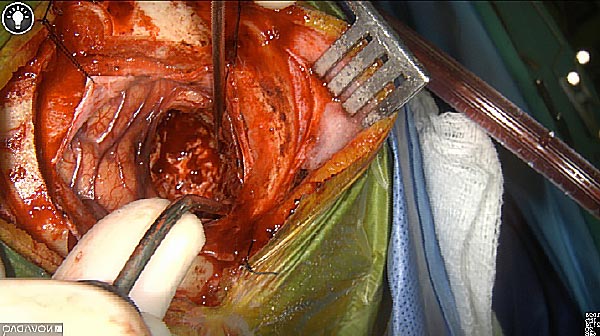

Wound bed post re-resection of tumor

Fluorescence imaging of the tumor was performed prior to resection and after resection to “check” the wound bed. In the upper row the tumor is clearly visible with fluorescence and in the bottom row you can see that the wound bed is empty – there is no suspicious fluorescence left. The middle column of tiles show the fluorescence signal in black and white where the “white” represents the tumor and the black the background (= no fluorescence signal). The right column of tiles shows the overlay of the brightfield photo (in greyscale) and the fluorescence (red-yellow-blue heatmap). This image provides anatomical context to the surgeon – the surgeon can see where is the fluorescence located with regard to the tumor area.

White light

Fluorescence (heat map)

Fluorescence (black and white)